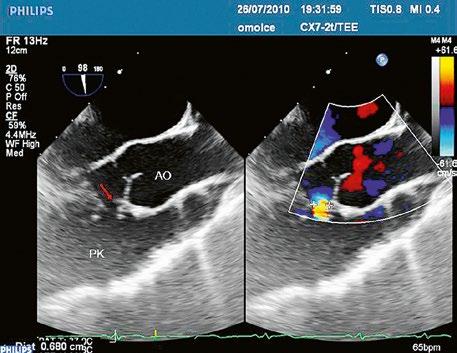

Obr. 45.36 Valvární pulmonální stenóza, doming cípů, jemné cípy, srůst komisur (TEE, longitudinální projekce) AP – kmen plicnice, PK – pravá komora, PS – pravá síň

valvuloplastika, a to bez ohledu na symptomy, při gradientu nad 64 mmHg; u symptomatických pacientů i při nižším gradientu.

z U dysplastických, kalcifikovaných významných valvárních PS, u subvalvárních PS nebo při současné těžké pulmonální regurgitaci je nutno volit chirurgickou léčbu při symptomech, dysfunkci pravé komory, arytmiích nebo pravolevém zkratu bez ohledu na gradient.

z U zcela asymptomatických pacientů nevhodných k balonkové valvuloplastice je chirurgická léčba indikována při gradientu nad 80 mmHg.